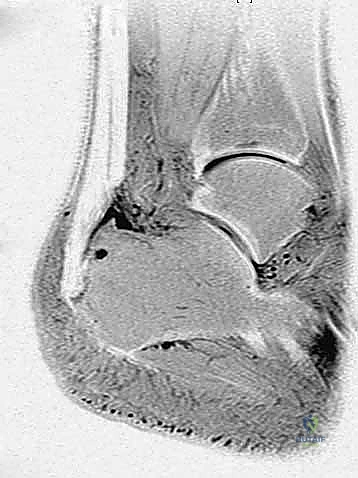

- التصوير بالرنين المغناطيسي (MRI): هو المعيار الذهبي لتقييم مدى تلف ألياف الوتر، حجم التمزقات الداخلية، ودرجة التهاب الجراب الزلالي. يساعد الرنين المغناطيسي الجراح في التخطيط المسبق للعملية بدقة.